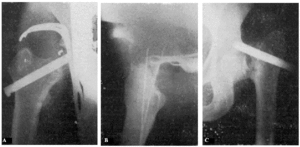

Fracaso número 2(observación número 2). F. S., setenta años4. Ingresa en el servicio con una fractura mediana del cuello femoral izquierdo. Osteosíntesis extraarticular (fig. 3. A y B). La impactación no ha resultado perfecta.

Figura 3. A: obs. núm. 2. El clavo no penetra suficientemente y la impactación, salvo en la parte superior de la línea de fractura, es muy defectuosa. B: obs. núm. 2. La posición del clavo es buena. C: obs. núm. 2. El clavo tiende a ser expulsado hacia fuera y apenas penetra en la cabeza femoral.

A los veinte días de la intervención pasa el enfermo a su domicilio, recomendándole que continúe en la cama. Pasado un mes vemos nuevamente al enfermo, el cual nos manifiesta que anda con mucha más dificultad que en los primeros días de permanecer en su domicilio, que fue cuando, por no haber interpretado bien nuestras indicaciones, comenzó a emprender la marcha. La radiografía (fig. 3. C) demuestra que el clavo apenas penetra en la cabeza femoral. A los ocho días hacemos otra radiografía (fig. 4. A), observándose que el trocáncer ha ascendido, a pesar de continuar guardando cama el enfermo. Ingresa nuevamente en el servicio, donde, con anestesia raquídea, retiramos el clavo, reduciendo las fracturas y volviendo a colocar un clavo más largo en buena dirección (fig. 4. B). Una radiografía practicada siete años y medio más tarde demuestra la no consolidación de la fractura, trastornos tróficos en cuello y cabeza femoral y que el cabo ha penetrado en el fondo de la cavidad cotiloidea, en donde ha labrado una cavidad (fig. 4. C).

Figura 4. A: obs. núm. 2. El trocánter ha ascendido francamente con relación a la radiografía anterior. El clavo tiende a salir de la cabeza por su parte superior. B: obs. núm. 2. Se extrajo el clavo y se colocó otro. El nuevo clavo está colocado en buena dirección, pero la reducción no es perfecta. C: obs. núm. 2. El clavo ha penetrado en el fondo de la cavidad cotiloidea, en cuyo lugar ha labrado una cavidad. Trastornos tróficos en cuello ycabeza femoral. El cuello del fémur ha desaparecido casi completamente.

En este caso el fracaso se debe a que la impactación no fue perfecta, y sobre todo, a haber el enfermo iniciado la deambulación al mes de intervenido, a pesar de que nosotros le ordenamos que guardara cama.